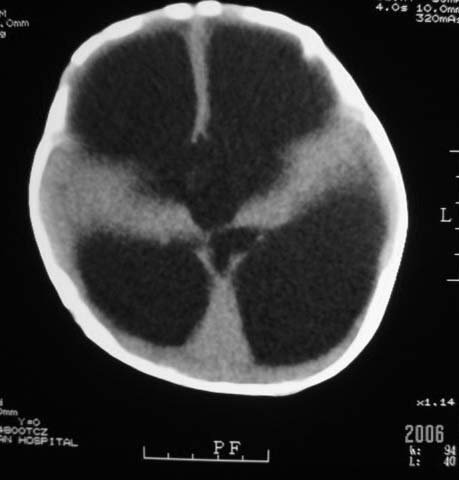

3m,出生时有新生儿吸入性肺炎、hie、化脓性脑膜炎,近一个月发现头围增大(51cm),无恶心呕吐。

1、重度脑积水;2、积水性无脑畸形。

3m,出生时有新生儿吸入性肺炎、hie、化脓性脑膜炎,近一个月发现头围增大(51cm),无恶心呕吐,脑室系统全程扩张,脑皮质变薄,结合病史考虑交通性脑积水

1、重度脑积水;2、积水性无脑畸形

3m,出生时有新生儿吸入性肺炎、hie、化脓性脑膜炎,近一个月发现头围增大(51cm),无恶心呕吐,脑室系统全程扩张,脑皮质变薄,结合病史考虑重度交通性脑积水。

积水性无脑畸形。